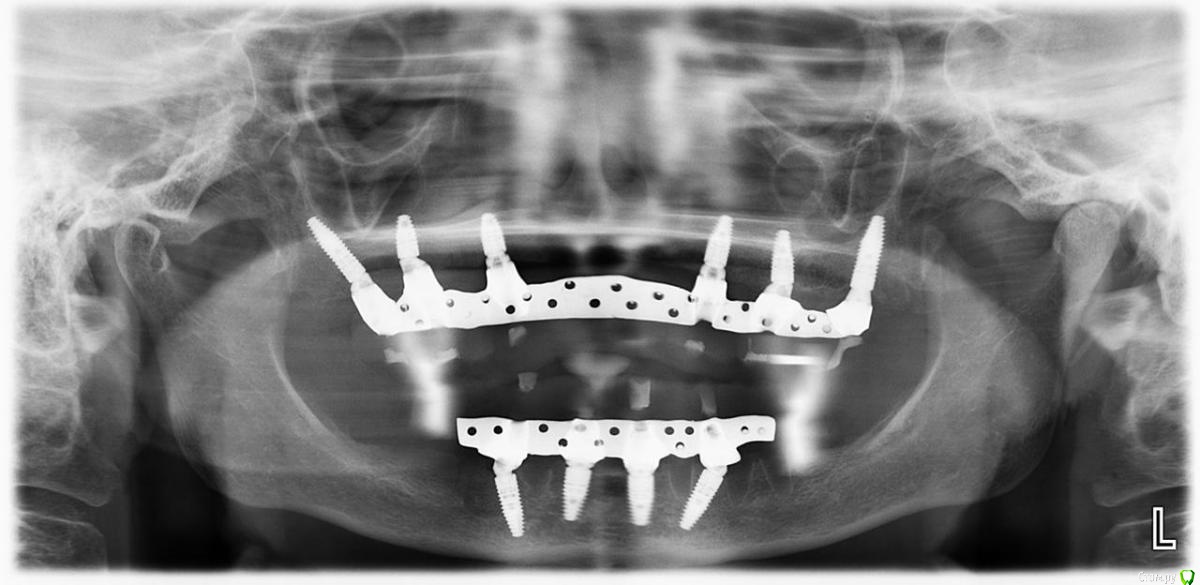

Дмитрий Л. Опубликовано 10 февраля, 2020 Поделиться Опубликовано 10 февраля, 2020 Ого, ну и высота!Сразу бросаются в глаза нижние дистальные мультиюниты. Зачем было располагать имплантат с дистальным наклоном, чтоб потом техник развернул мультиюнит мезиально? Уже можно было вертикально имплант вкрутить с таким успехом.Извините за придирки, в таких сложных работах только на мелочи и можно внимание обращать. Ссылка на комментарий

Bier Опубликовано 10 февраля, 2020 Автор Поделиться Опубликовано 10 февраля, 2020 Ого, ну и высота!Сразу бросаются в глаза нижние дистальные мультиюниты. Зачем было располагать имплантат с дистальным наклоном, чтоб потом техник развернул мультиюнит мезиально? Уже можно было вертикально имплант вкрутить с таким успехом.Извините за придирки, в таких сложных работах только на мелочи и можно внимание обращать.возможно это некоторая хирургическая погрешность, в виду отсутствия полного гайда.Мне кажется, что планировался бОльший наклон и соответственно подобран мультиюнит 30 градусов. В итоге получилось так, когда я во рту фиксировал мультиюниты, мне показалось, что все достаточно параллельно. (незначительные расхождения в градусах только улучшают фиксацию)Под углом имплантат ставится для того, чтобы можно было выбрать более длинный и обеспечить бОльшую первичную стабильность, ведь пока имплантаты не прижились размер имеет значение. Ну и я обошел ментальные отверстия, разместив платформу дистальнее. Ссылка на комментарий